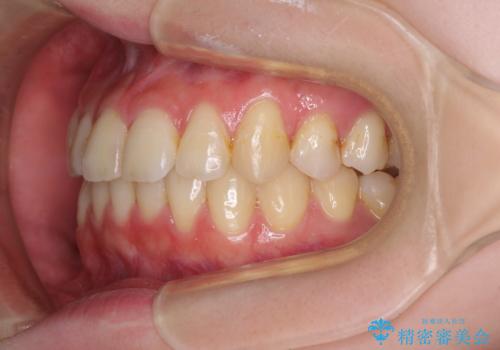

- 上下前歯のデコボコを気にして来院された患者様です。

以前矯正をした後戻りということで、歯列不正はそれほど大きくなかったため、インビザライン・ライトを用いて矯正治療を行うこととしました。

前歯のデコボコが残っており、シミュレーション通りに動いていない部分がありましたが、再矯正であることやご本人の満足いくところまでデコボコが改善されたとのことで、治療を終了することとしました。